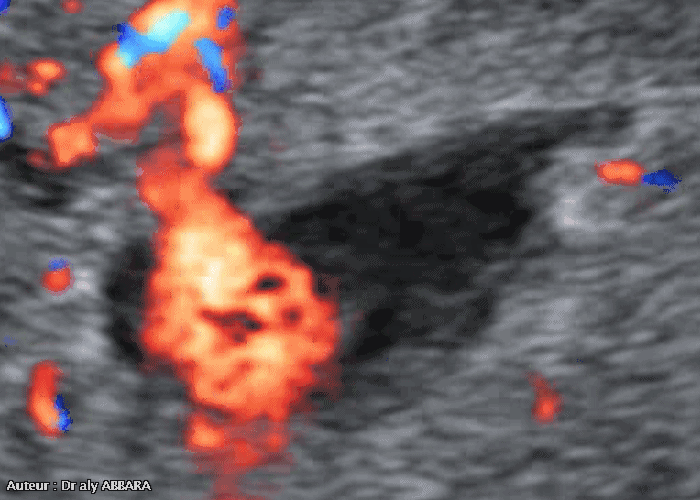

Caverne placentaire : aspect échographique avec Doppler couleur - tourbillons sanguins

• Image échographique animée avec Doppler couleur (Dynamic-Flow) montrant l'aspect ultrasonore d'une caverne placentaire :

• Il s'agit d'un lac intraplacentaire siégeant au centre d'un cotylédon et prenant la forme d'une lacune hétéroéchogène à contours irréguliers et un peu flous ; le contenu est animé par des flux sanguins lents et tourbillonnants accélérés par des jets artériels provenant de la circulation maternels vers les chambres intervillositaires.

• L'étude de ces flux permet l'obtention d'un signal Doppler continu tourbillonnant par l'éjection du sang maternel, à certains points périphériques, vers la cavité de cette caverne placentaire (comme dans la chambre cylindrique d'un moteur).

• Il s'agit d'une zone de régression villositaire localisée, intraplacentaire.

• A ne pas confondre avec l'hématome rétroplacentaire central.

• Les images publiées dans cette page ont été réalisées chez une femme enceinte de 37,3 semaines d'aménorrhée.